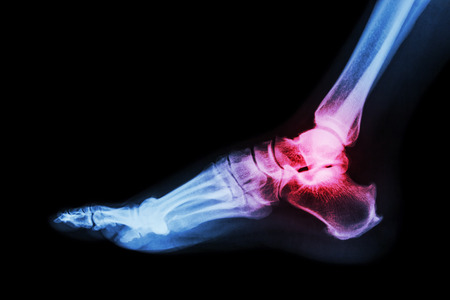

A fracture is a break in the bone, as opposed to a soft tissue injury such as a sprain or strain. A stress fracture is a tiny bone break caused by overuse, and often developing over time rather than suddenly.

Your podiatrist will assess your injury with imaging tests such as an X-ray. An ultrasound or MRI can help diagnose stress fractures as well as soft tissue injuries.